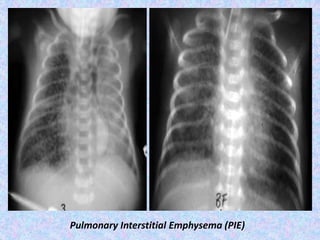

Pulmonary interstitial emphysema.

Pulmonary interstitial emphysema (PIE) refers to the abnormal location of air

within the pulmonary interstitium and lymphatics. It typically results from rupture

of overdistended alveoli following barotrauma in infants who have respiratory

distress syndrome. Interstitial emphysema can also occasionally be incidentally

detected in adults.

Radiographic features

Plain film - chest radiograph shows bubbles (round) or streaky (linear)

radioculencies in the interstitium radiating from the hilum . Affected segment is

often hyperexpanded and static in volume on multiple radiographs. Patients may

have pneumothorax, pneumomediastinum, or pneumopericardium in supine

patients, pneumomediastinum is evident by the sharp mediastinum sign

CT chest

shows cystic radioculencies in affected segment may characteristically show a line

and dot pattern with pulmonary arterial branches surrounded by radiolucent air

may help differentiate persistent PIE from a hyperlucent mass such as congenital

lobar emphysema, congenital pulmonary airway malformation (CPAM)

allows better visualization of a pneumothorax or pneumomediastinum

if incidentally detected in adults, it may appear as perivascular lucent or low-

attenuating halos and small cysts.

Pulmonary Interstitial Emphysema (PIE)